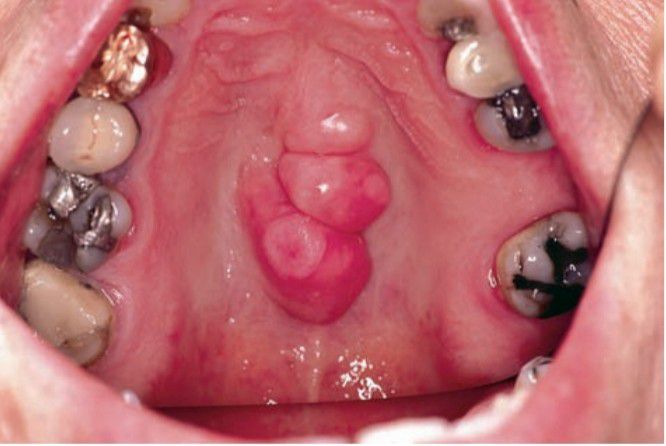

Torus palatinus

The palatal torus is a sessile, nodular mass of bone that appears along the midline of the hard palate. This lesion occurs in females twice as often as it does in males.